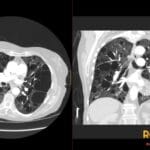

Diagnosis: Appendiceal Mucocele

- CT: Round or tubular low-attenuation (17-26 HU) cystic mass near water density; well-encapsulated; wall calcification is a strong diagnostic feature; wall irregularity and mural nodularity suggest malignancy (cystadenocarcinoma).

- Signs: Onion-Skin Sign: Pathognomonic ultrasound finding of multiple echogenic layers; Whorly/Onion Peel Appearance: CT description of layered mucin within the dilated lumen.